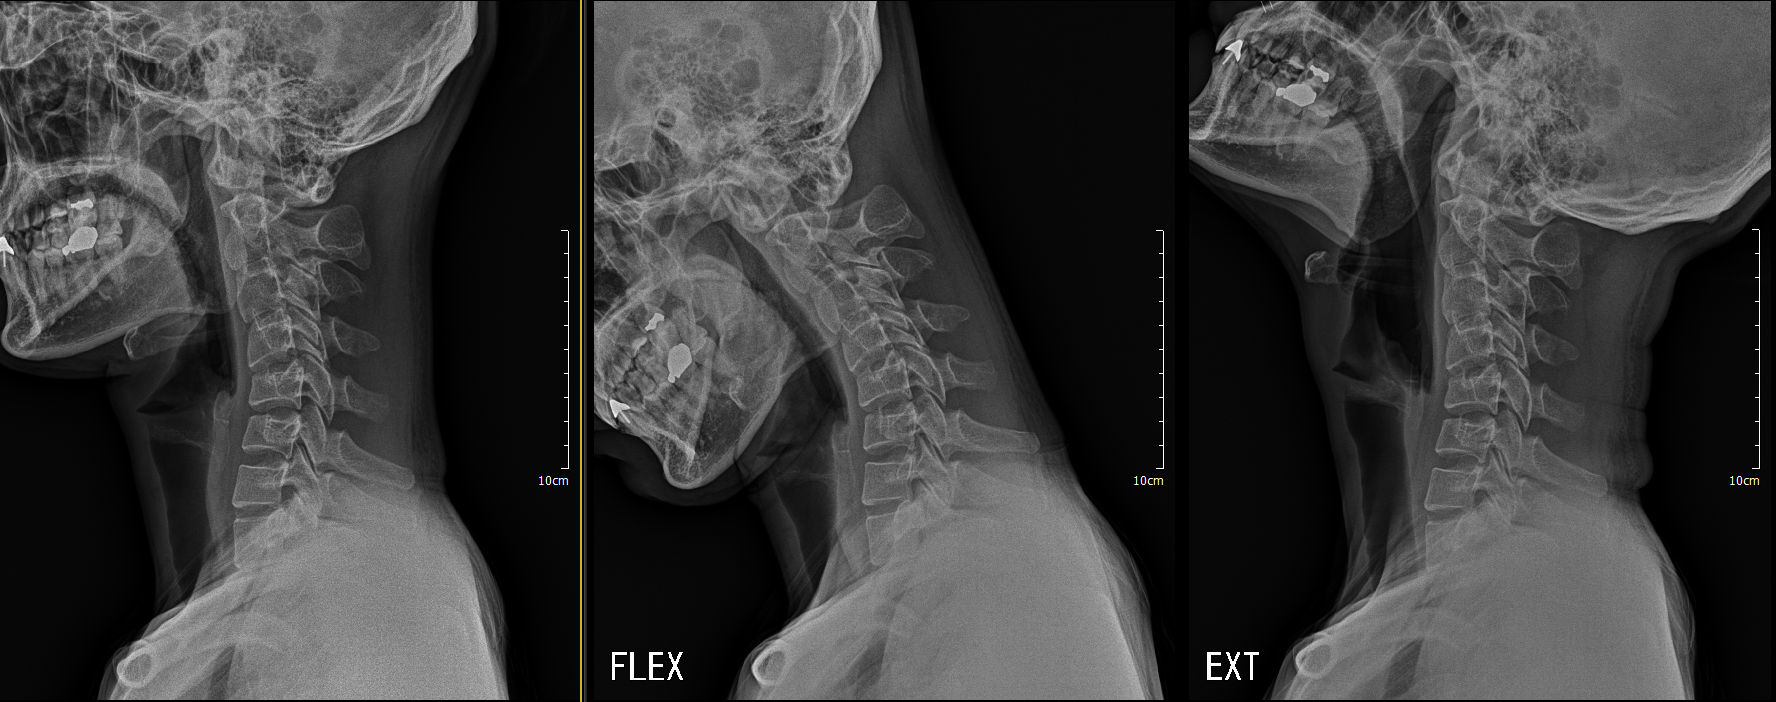

거북목 x ray 추가

목이 정상적이라면, C자 형태의 곡선으로 이룹니다. 하지만 요즘은 스마트폰과 컴퓨터 사용량이 증가함에 따라 고개를 앞으로 쭉 숙이거나 오랫동안 숙이는 잘못된 자세를 유지하거나 외부 충격으로 인해 목 근육이 경직되면, 일자형 또는 역 C자 형태 곡선을 이루게 됩니다. 이에 따라 젊은 연령층에서도 목이 딱딱해지고 통증을 느끼고 어깨까지 통증이 느껴지는 거북목 증후군을 앓는 분들이 늘어나고 있습니다. 또한 해당 질환은 현대인들의 만성질환이라고 불릴 정도로 많은 분이 많이 겪는 질환 중 하나인데, 이에 따라 증상을 발견하더라도 방치하는 경우가 많아 여러 통증과 목 디스크 등과 같은 2차 질환을 유발하게 됩니다.